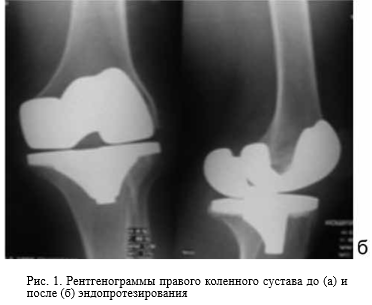

Всем пациентам при поступлении в стационар в первую очередь проведено рентгенологическое исследование коленного сустава с использованием цифровой системы, исследование проводилось до и после операции эндопротезирования (рис. 1).

Рентгенографию коленных и тазобедренных суставов до и после операции эндопротезирования проводили на цифровом рентгеновском аппарате «Siеmens».